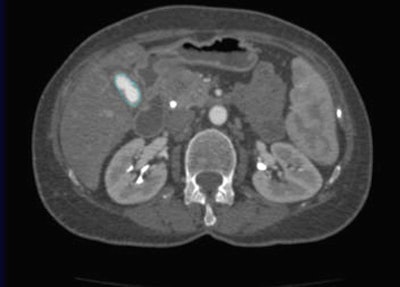

![]() |

| The margins of the gallbladder, here outlined by positive oral contrast post ERCP, are manually traced. All images courtesy of Dr. Darren Brennan. |